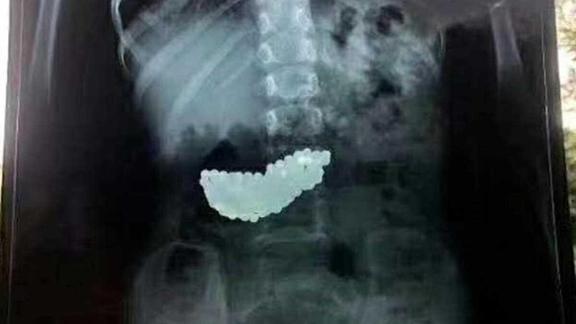

Çin'de inanılmaz olay: 5 yaşındaki çocuğun midesinden 190 bilye çıktı

Çin'de akıllara durgunluk veren bir haber basına yansıdı. Bir çocuğun midesinden, 190 adet mıknatıslı bilye çıkartıldı. 5 yaşındaki çocuğun, oyun oynarken bilyeleri yuttuğu ve 2 ay boyunca midesinde bu bilyelerle yaşadığı ortaya çıktı.

Mıknatıslı olan bilyeler çocuğun midesinde biraraya gelerek büyük bir kitle haline geldi. Bilyeler doğal yollardan çıkmayınca küçük kız 2 ay bu kitleyle yaşadı. Doktorlar rontgenle tespit ettikleri kitleyi ameliyatla çıkardı.